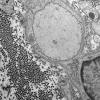

PERIPHERAL NEUROPATHY

6 AXONAL DEMYELINATION (BASIC PROCESS)